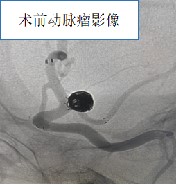

患者刘女士,2024年2月26日以“突发头颈部剧痛4小时”为主诉急诊入院。头颅CT提示自发性蛛网膜下腔出血,拟急诊行全脑血管造影术,但患者既往有脾大病史,入院血常规提示该患者有手术禁忌症。但患者高度怀疑颅内动脉瘤破裂,如果再次破裂患者随时发生生命危险。神经外科许刚、张明副主任医师经讨论先给患者行相对创伤较小的CTA检查,排查患者是否脑动脉瘤破裂,同时先予以升高血小板等对症治疗。然而很不幸的是患者CTA提示为不仅左侧后交通大动脉瘤破裂,而且还是胚胎型大脑后动脉,这就意味着患者可能需要双支架辅助技术进行栓塞,那么围手术期抗血小板治疗必不可少,但面对这么低的血小板术中肝素化及抗血小板治疗患者动脉瘤再次破裂出血风险极大,因此脑血管病亚专业组团队经讨论后提交了MDT多学科会诊申请。

3月1日,由医务部牵头,门诊多学科办公室范艳梅副主任护师、陈扬扬护师组织,由神经外科许刚、张明副主任医师、血液科赵万宏主任医师、干四病区张健副主任医师、药学部张莉主管药师、检验科张磊副主任技师、风湿免疫科赵辉主治医师进行MDT多学科会诊,最终意见:患者为免疫性血小板减少症,目前存在神经外科手术禁忌症,先予以升高血小板治疗,并做好血小板计数及凝血功能、血栓弹力图监测,一旦血小板达标,尽早手术。经过5天的精心准备及详细监测,患者的血小板终于达标。遂于2024年3月5日,麻醉医师张鹏施行全麻插管,由神经外科许刚、张明副主任医师主刀、屈满利护师协助为患者行后交通动脉瘤“T”型支架辅助动脉瘤栓塞术,手术计划一枚支架放入颈内动脉保护颈内动脉,一枚支架放入后交通动脉,保护后交通动脉,两枚支架精准交汇于瘤颈部位,稍有偏差则手术失败,然后栓塞动脉瘤。术中两位术者仔细测量,精准定位,支架释放满意,动脉瘤栓塞致密,大脑后动脉保护良好。术后予以静脉使用抗血小板药物桥接口服抗血小板药物,每日在张磊副主任技师的密切监测指导下,动态调整抗血小板药物剂量,术后患者血小板数量及功能正常,血栓弹力图提示抗血小板治疗达标。术后患者恢复满意,已于近日康复出院。